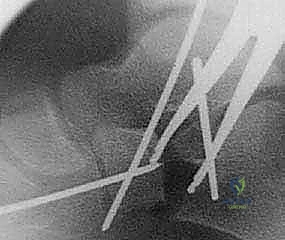

3. القطع العظمي (The Osteotomy)

باستخدام منشار جراحي دقيق، يتم إجراء قطع في عظم الكعب (Calcaneus). يتم تحديد مكان القطع بدقة بالغة، عادةً على بعد حوالي 1.5 سم خلف المفصل العقبي النردي (Calcaneocuboid Joint). يحرص الدكتور هطيف على الحفاظ على القشرة العظمية الداخلية (Medial Cortex) سليمة لتكون بمثابة مفصلة (Hinge) تمنع عدم استقرار العظم.

5. التثبيت الداخلي (Internal Fixation)

لضمان عدم تحرك الطعم العظمي أثناء فترة الالتئام، يتم تثبيت التكوين الجديد. يستخدم الدكتور هطيف أحدث تقنيات التثبيت، والتي قد تشمل شريحة معدنية صغيرة مع مسامير (Plate and Screws)، أو مسامير معدنية تمر عبر العظم، أو أسلاك كيرشنر (K-wires)، وذلك لضمان أقصى درجات الثبات الميكانيكي.

يتم التأكد من صحة التثبيت والتصحيح باستخدام جهاز الأشعة السينية المباشر (C-arm Fluoroscopy) داخل غرفة العمليات قبل إغلاق الجرح.